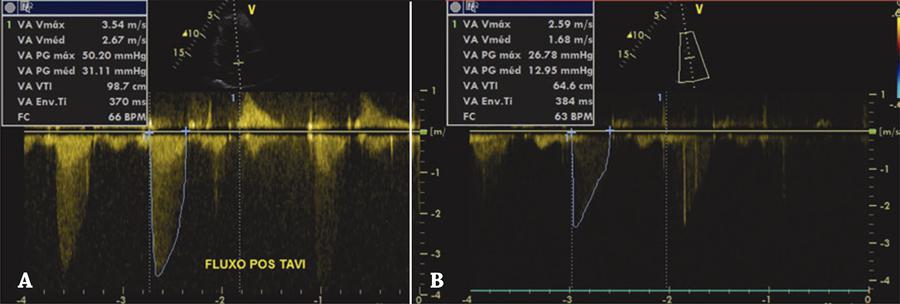

Figura 4

Gradiente transvalvar aórtico. (A) Controle ecocardiográfico evidenciando o gradiente após o implante da prótese transcateter; (B) queda importante do gradiente após a dilatação com o balão.